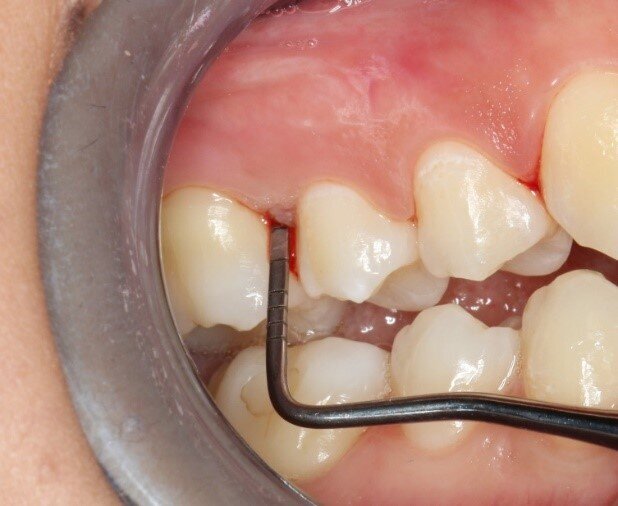

A una settimana dall’applicazione, i pazienti riferiscono una riduzione significativa di sanguinamento e sensibilità gengivale, con risultati superiori rispetto alla sola pulizia professionale. Nei casi di gengivite e tasche parodontali fino a 3 mm, UBIGEL INPERIO ha dimostrato di favorire una parziale o completa regressione dell’infiammazione, contribuendo al ripristino dell’attacco epiteliale e all’eliminazione del sanguinamento grazie alla sua azione antibatterica mirata. Nella Figura 1 è mostrata la situazione iniziale del paziente prima del trattamento.Dopo una settimana dall’applicazione di Ubigel Inperio (Fig. 2), si osservano i primi miglioramenti clinici. Il sondaggio pre-trattamento, effettuato sette giorni dopo l’igiene professionale, evidenziava una profondità di 3 mm con presenza di sanguinamento gengivale (Fig. 3). A distanza di 21 giorni dal trattamento, il sondaggio mostra una profondità della tasca inferiore a 2 mm e l’assenza di sanguinamento, segno di un netto miglioramento dello stato gengivale (Fig. 4).